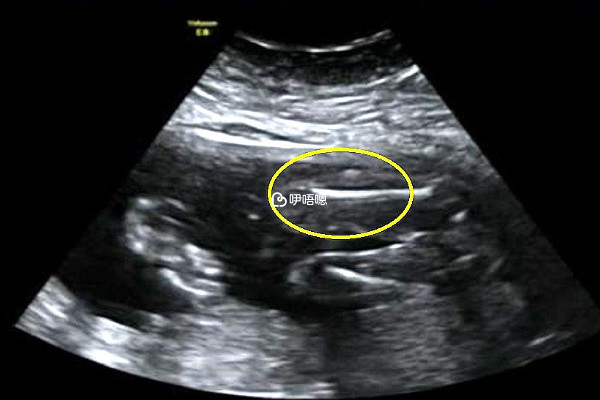

孕7周孕囊大小標準值應該在2.5到3cm之間,而孕囊太大胎芽偏小屬於胚胎髮育不良的一種B超表現,這種大孕囊是不正常的,所以容易胎停流產。這與胚胎質量不好、母體內分泌紊亂、凝血功能異常、免疫因素等有一定的關係,相當一部分大孕囊患者在檢查後1-2週會出現宮腔積液,進而導致流產率增加,因此大孕囊胎停機率高。一下是孕囊太大胎停的原因分析,大家可以瞭解一下:

總之,孕囊太大胎停機率是很高的,孕婦想要順利妊娠一定要按時產檢,當B超檢查發現大孕囊時應注意休息,避免受涼、勞累,儘早查明原因,積極保胎治療。除胚胎問題外,經過正規醫生指導保胎,通常可繼續妊娠。